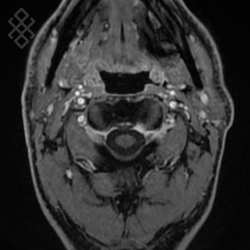

IRM des Parotides

La durée moyenne de l'examen est de 35 min. Dans le cas d'une injection, le manipulateur en radiologie vous administrera le produit de contraste. Vous entendrez un bruit caractéristique à l'IRM faisant penser à un marteau piqueur. Pendant certaines séquences, pour limiter les mouvements de déglutition, il ne faudra pas avaler la salive.